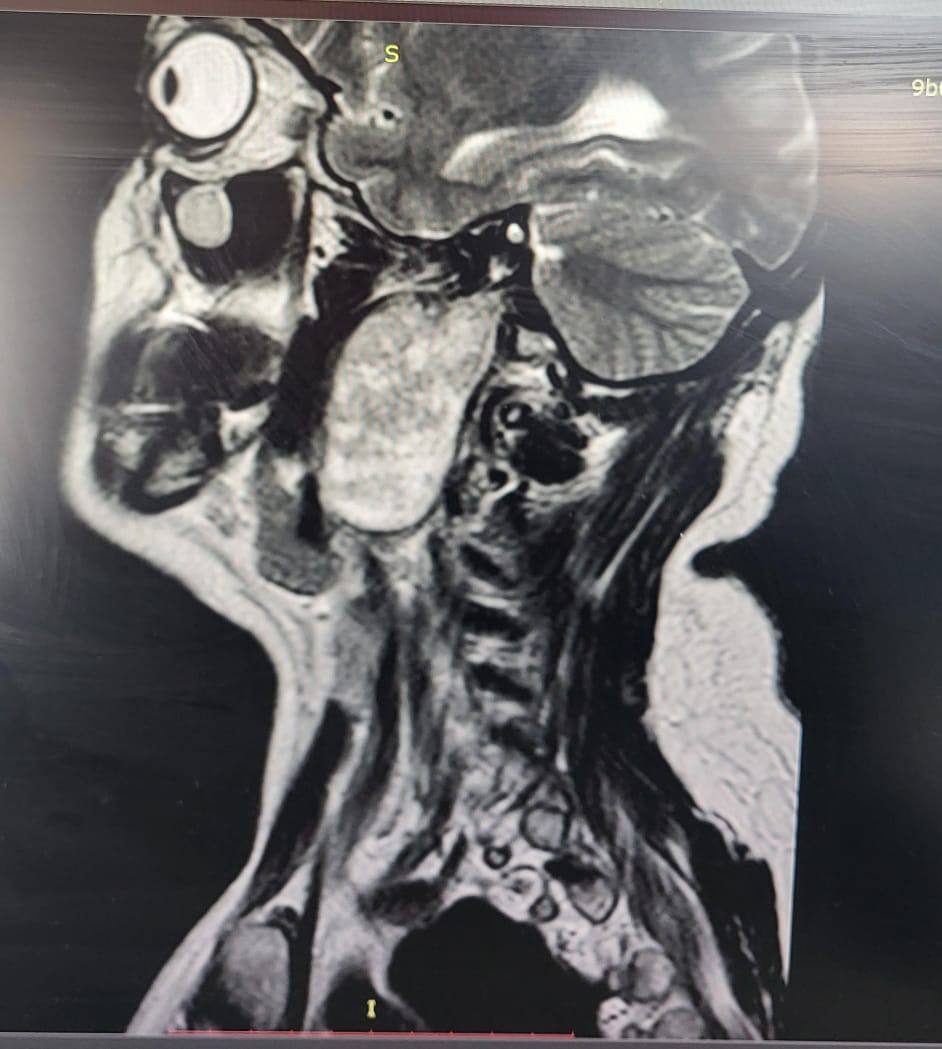

Сложную опухоль сумели прооперировать врачи ККБ №1 в Хабаровске

Женщина жаловалась на заложенность уха и увеличение небной миндалины. Результаты исследований выявили у нее в голове объемное образование. Это оказалась шваннома – доброкачественная опухоль, которая развивается из оболочек нервных клеток.